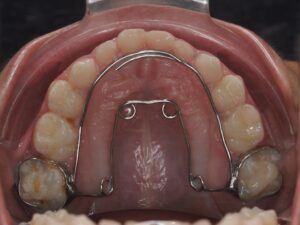

Il correspond au maintien ou à la réouverture des espaces afin que les dents définitives puissent évoluer.

Les dents de lait sont souvent sous-estimées mais elles jouent un rôle primordial dans l’éruption des dents définitives. Il faut savoir que la nature n’aime pas le vide, une perte prématurée d’une « dent de lait » entrainerait un risque d’absence de place pour la « dent d’adulte ». Il peut donc être nécessaire de maintenir ou de rouvrir certains espaces.

Il s’agit de la mastication, la respiration, la posture linguale, les habitudes déformantes. Elles font partie intégrante de la bonne posture des mâchoires et des dents. Elles seront également contrôlées et interceptées. Les appareils sont nombreux en fonction de la malocclusion, ils peuvent être fixes ou amovibles. Très souvent, l’interception pourra être associée à un rendez-vous chez : l'ORL, l'orthophoniste, le kinésithérapeute ou encore l'osthéopathe.